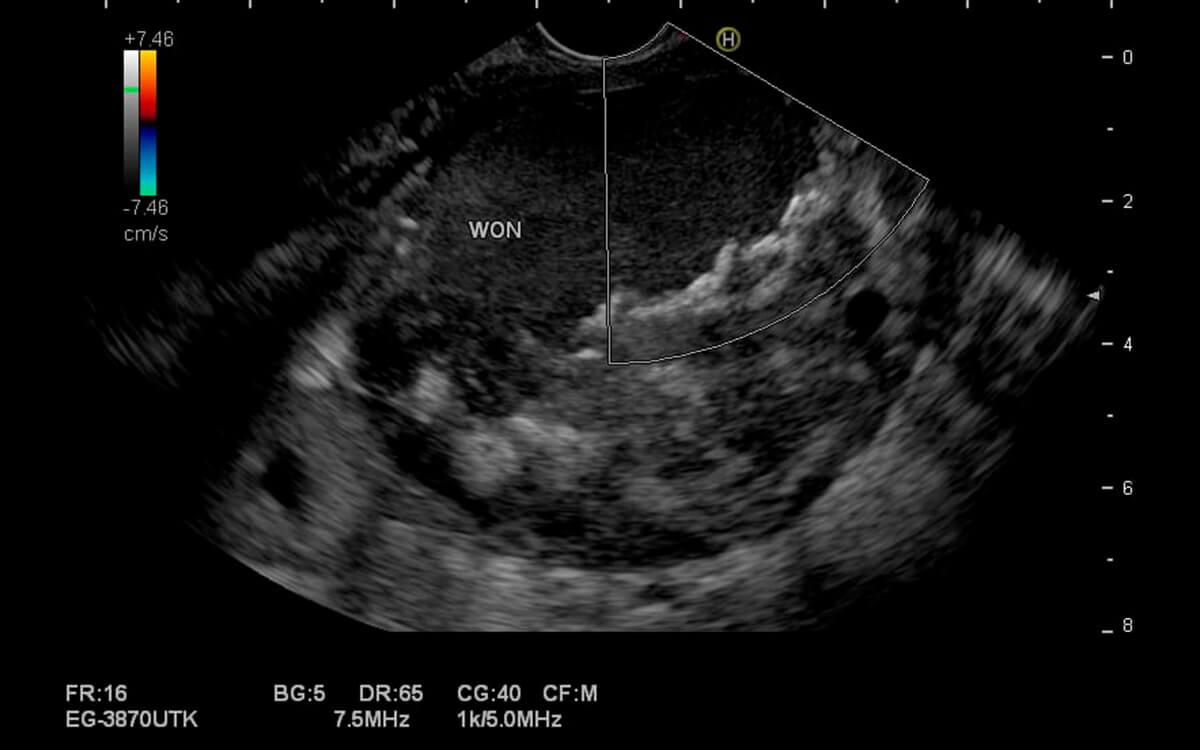

A Ecoendoscopia Terapêutica , é um exame diagnóstico e potencialmente terapêutico do trato digestivo alto e baixo. O médico endoscopista pode analisar o esôfago, estômago, duodeno, pâncreas, vias biliares, vesícula biliar, fígado, intestino (cólon) e reto com um ultrassom, através de acesso por endoscopia (ecoendoscopia alta) ou colonoscopia (ecoendoscopia baixa).

O Dr. Hugo Guedes, médico especialista em Ecoendoscopia Terapêutica pela USP e do Hospital Sírio Libanês, explica que "a ecoendoscopia possibilita examinar camadas mais profundas dos órgãos digestivos, que não poderiam ser avaliadas apenas pela endoscopia comum, pois esta permite apenas a visualização superficial de suas paredes internas".

Ecoendoscopia Terapêutica faz o exame ultrassonográfico do aparelho digestivo, além de permitir a realização de punção por agulha diretamente desses órgãos (ecoendoscopia com biópsia). Dessa forma, podemos analisar diversas doenças do trato digestivo, como:

- cistos pancreáticos e biliares;

Durante o exame é possível ainda realizar procedimentos terapêuticos e a coleta de pequenos fragmentos de tecidos, com pinças para biópsia ou punção por agulha, sendo que esses materiais serão enviados posteriormente para análise anatomopatológica em laboratório.